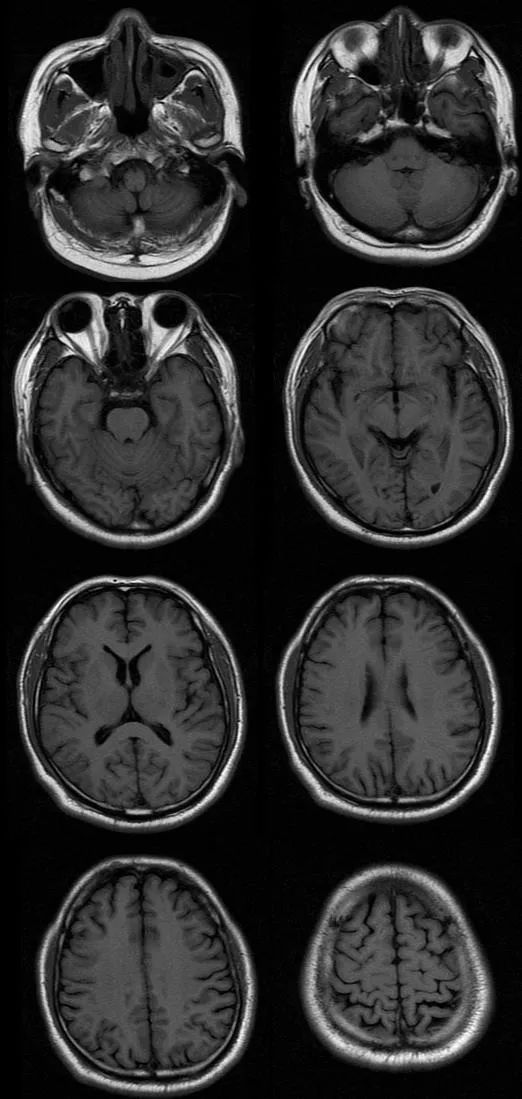

遗憾的是胸腰部 MRI 中 T1、T2、STIR 均未见明显异常,我们进一步完善头部 MRI,如下图:

T1

从影像学可以看出 T2FLAIR、T1、T2 似乎也未见明显异常,此时该如何诊断,定位到底在哪里呢?

让我们再仔细看一下 DWI:

DWI 提示右侧延髓背外侧小点状高信号,弥散受限,提示急性脑梗死。